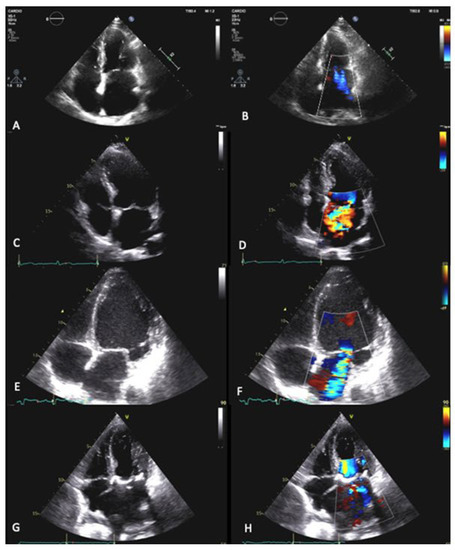

8 pages, 6823 KB

Novel 3D Echocardiographic Technique for Mitral Calcium Mapping

by Francesca Romana Prandi, Francesco Romeo, Francesco Barillà, Samin Sharma, Annapoorna Kini and Stamatios Lerakis

J. Clin. Med. 2023, 12(4), 1470; https://doi.org/10.3390/jcm12041470 - 12 Feb 2023

Cited by 2 | Viewed by 2380

Abstract

Mitral annular calcification (MAC) is a common chronic degenerative process of the mitral valve fibrous support ring. MAC increases the risk of mitral valve dysfunction, all-cause and cardiovascular mortality, and worse outcomes in cardiac interventions. Echocardiography represents the first imaging modality for MAC [...] Read more.

Mitral annular calcification (MAC) is a common chronic degenerative process of the mitral valve fibrous support ring. MAC increases the risk of mitral valve dysfunction, all-cause and cardiovascular mortality, and worse outcomes in cardiac interventions. Echocardiography represents the first imaging modality for MAC assessment, but it has low specificity compared to cardiac CT in terms of distinguishing between calcium and dense collagen. Novel three-dimensional transesophageal maximal intensity projection (MIP) mapping allows for the real-time MAC distribution and depth visualization of the cardiac anatomy and represents a useful and promising tool for pre-procedural assessment and intra-procedural guidance of cardiac interventions. Full article

(This article belongs to the Special Issue Mitral and Tricuspid Valve Disease and Imaging Techniques)

Show Figures

Figure 1